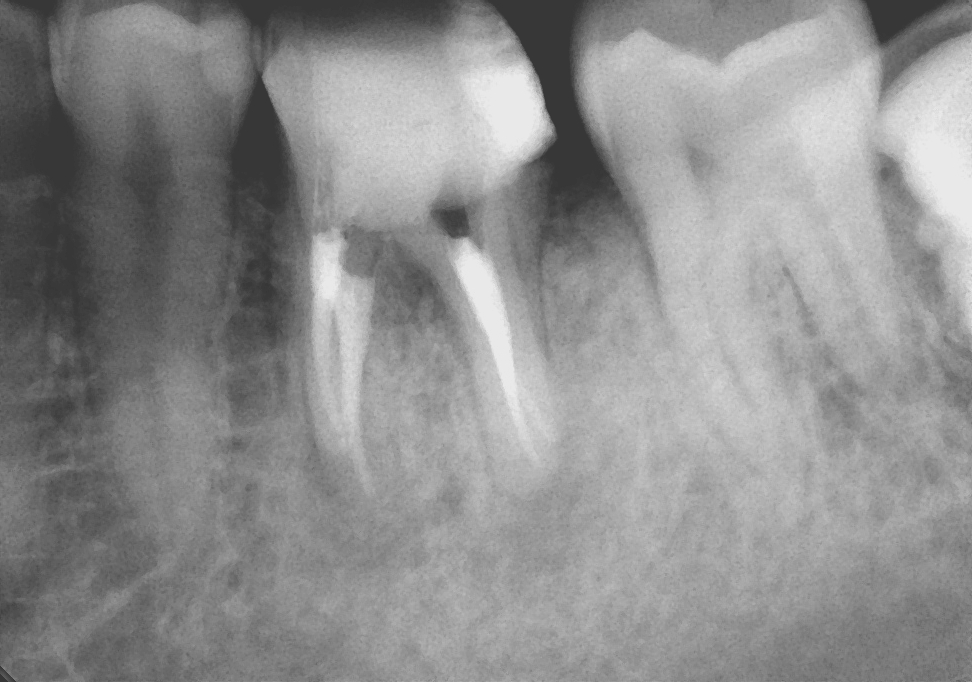

先日、いつもの3ヶ月毎の定期検診にお越しいただき、全体のチェックと共に根管治療部位のレントゲン写真も撮らせていただきました。

この10年症状も無く、もちろん新たなむし歯を作ることなく経過良好で過ごしていただいております。

ここまできて私もホッと一安心といったところです。治療において知識や技術の習得には終わりはありません。私も自分の伸びしろ信じ、多くの患者様に笑顔が戻るように日々精進していきたいと思います。